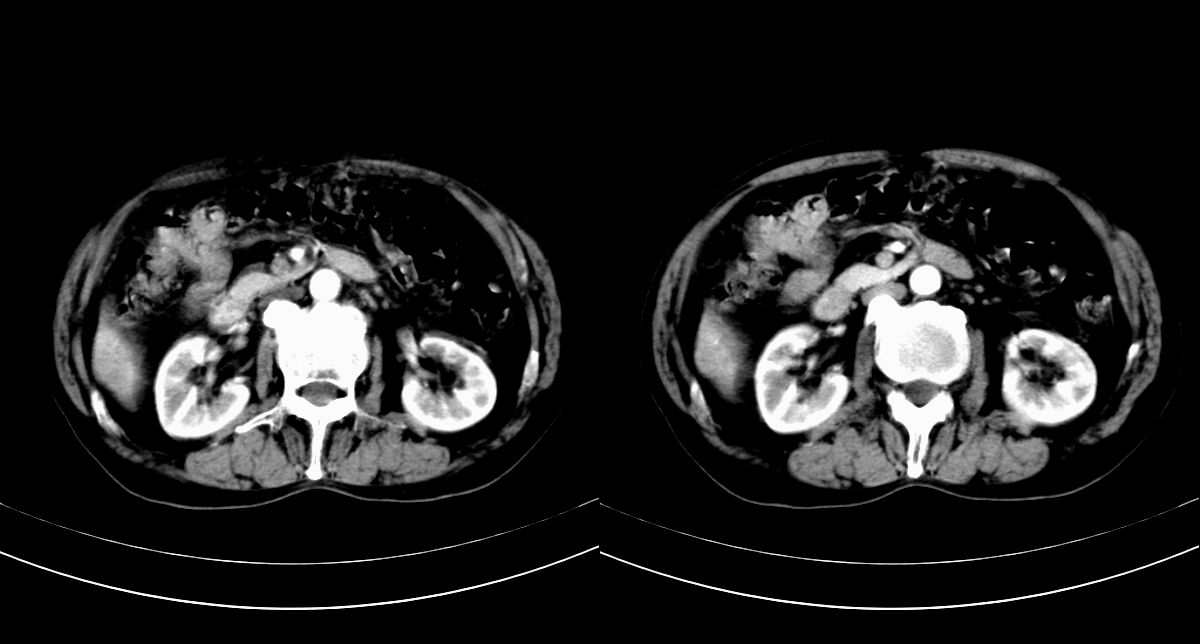

男,79y,无不适。体检发现肝脏占位。

肝内多发低密度结节,增强动脉期明显强化,门脉期逐渐下降,内有液化坏死区。

诊断:

肝细胞癌(结节型)

鉴别:肝转移癌。

支持多发结节巨块型肝癌,建议查afp。

巨块型肝癌伴肝内转移.

肝内多发低密度结节灶,增强动脉期明显不规则环状强化,;门脉期逐渐下降,肿瘤壁厚薄不一,内有坏死液化区。

诊断:典型的肝转移癌

支持多发结节巨块型肝癌。